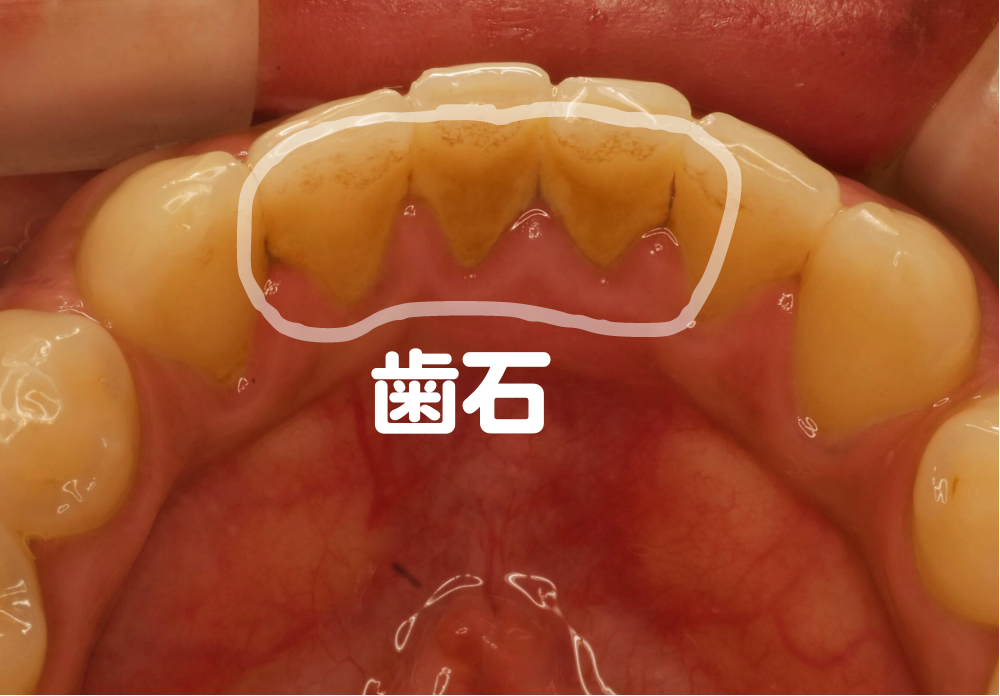

歯石(歯石としても知られています)は、歯垢と唾液からのミネラルが蓄積して固まったものです。歯石は歯の外側を覆い、歯肉縁の下に侵入することがあります。歯石は歯の上でカサカサした毛布のように感じられます。多孔質なので食べ物や飲み物で歯石がつきやすいです。

歯石の沈着物は歯の後ろや歯の間に沈着することが多く、黄色または茶色に見えます。歯石とその前駆体であるプラークは、どちらも歯の健康に悪影響を与える可能性があります。